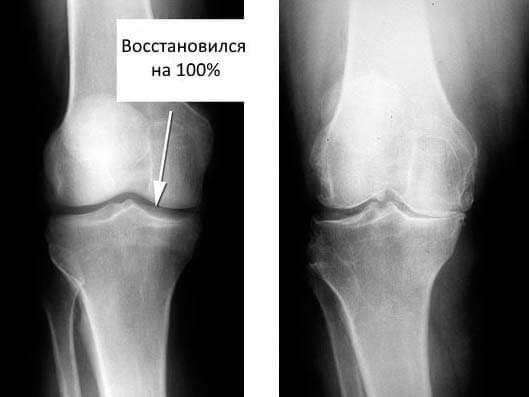

3-4 неделя. Организм будто очистился — хруст в коленях ушёл, суставы стали подвижнее. Каждое движение давалось легче, и я почувствовала, что идёт настоящий процесс восстановления.

5-6 неделя. Запустилась регенерация. Связки стали эластичными, хрящи перестали «ломаться» при нагрузках. Я решилась выйти на лёгкие тренировки и впервые за долгое время почувствовала радость от движения.

7-8 неделя. Нормализовались кровообращение и обменные процессы. Суставы работали свободно, я уже могла полноценно тренироваться. Боли не было, тело стало слушаться меня.